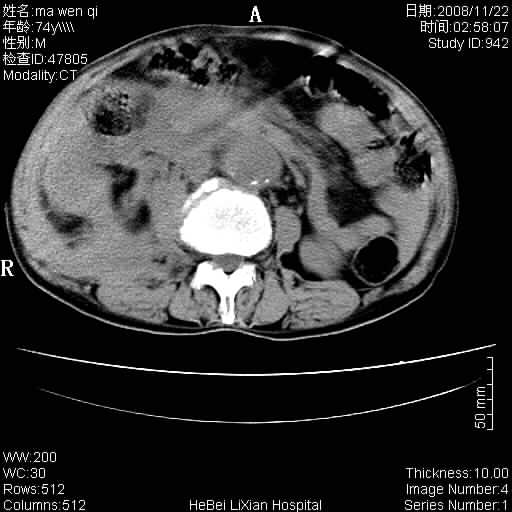

患者男 74岁.突然昏迷,休克6小时.血压70/30,头颅ct未见异常,既往体健.

补充病史,保留导尿10小时,尿袋内只有少许尿液,患者于住院后15小时后去世.

腹主动脉、双侧髂动脉夹层动脉瘤破裂出血进入腹腔。

1)考虑双侧髂动脉瘤并右侧动脉瘤破裂出血,右侧腹膜后及腹腔积血。2)双侧腹股沟疝。

1)考虑,腹主动脉、双侧髂动脉夹层动脉瘤破裂伴右侧腹膜后及腹腔积血。2)双侧腹股沟疝。